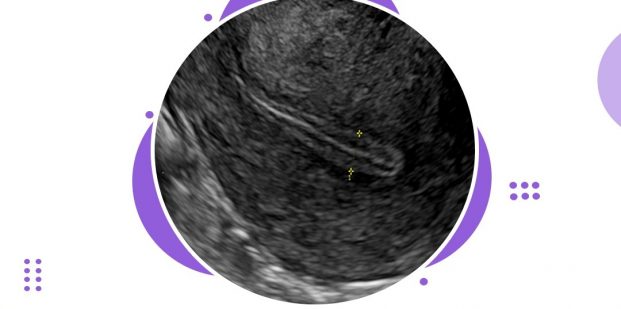

Ultrasound is the most common way to measure the thickness of the endometrium. Very rarely when ultrasound is not suitable, often due to the position of a person’s uterus or other health conditions, doctors use MRI.

The endometrium thickness is best seen on Transvaginal scans and is measured from echogenic border to echogenic border across the endometrial cavity on a sagittal midline image. Endometrium thickness plays an important role in successful implantation.